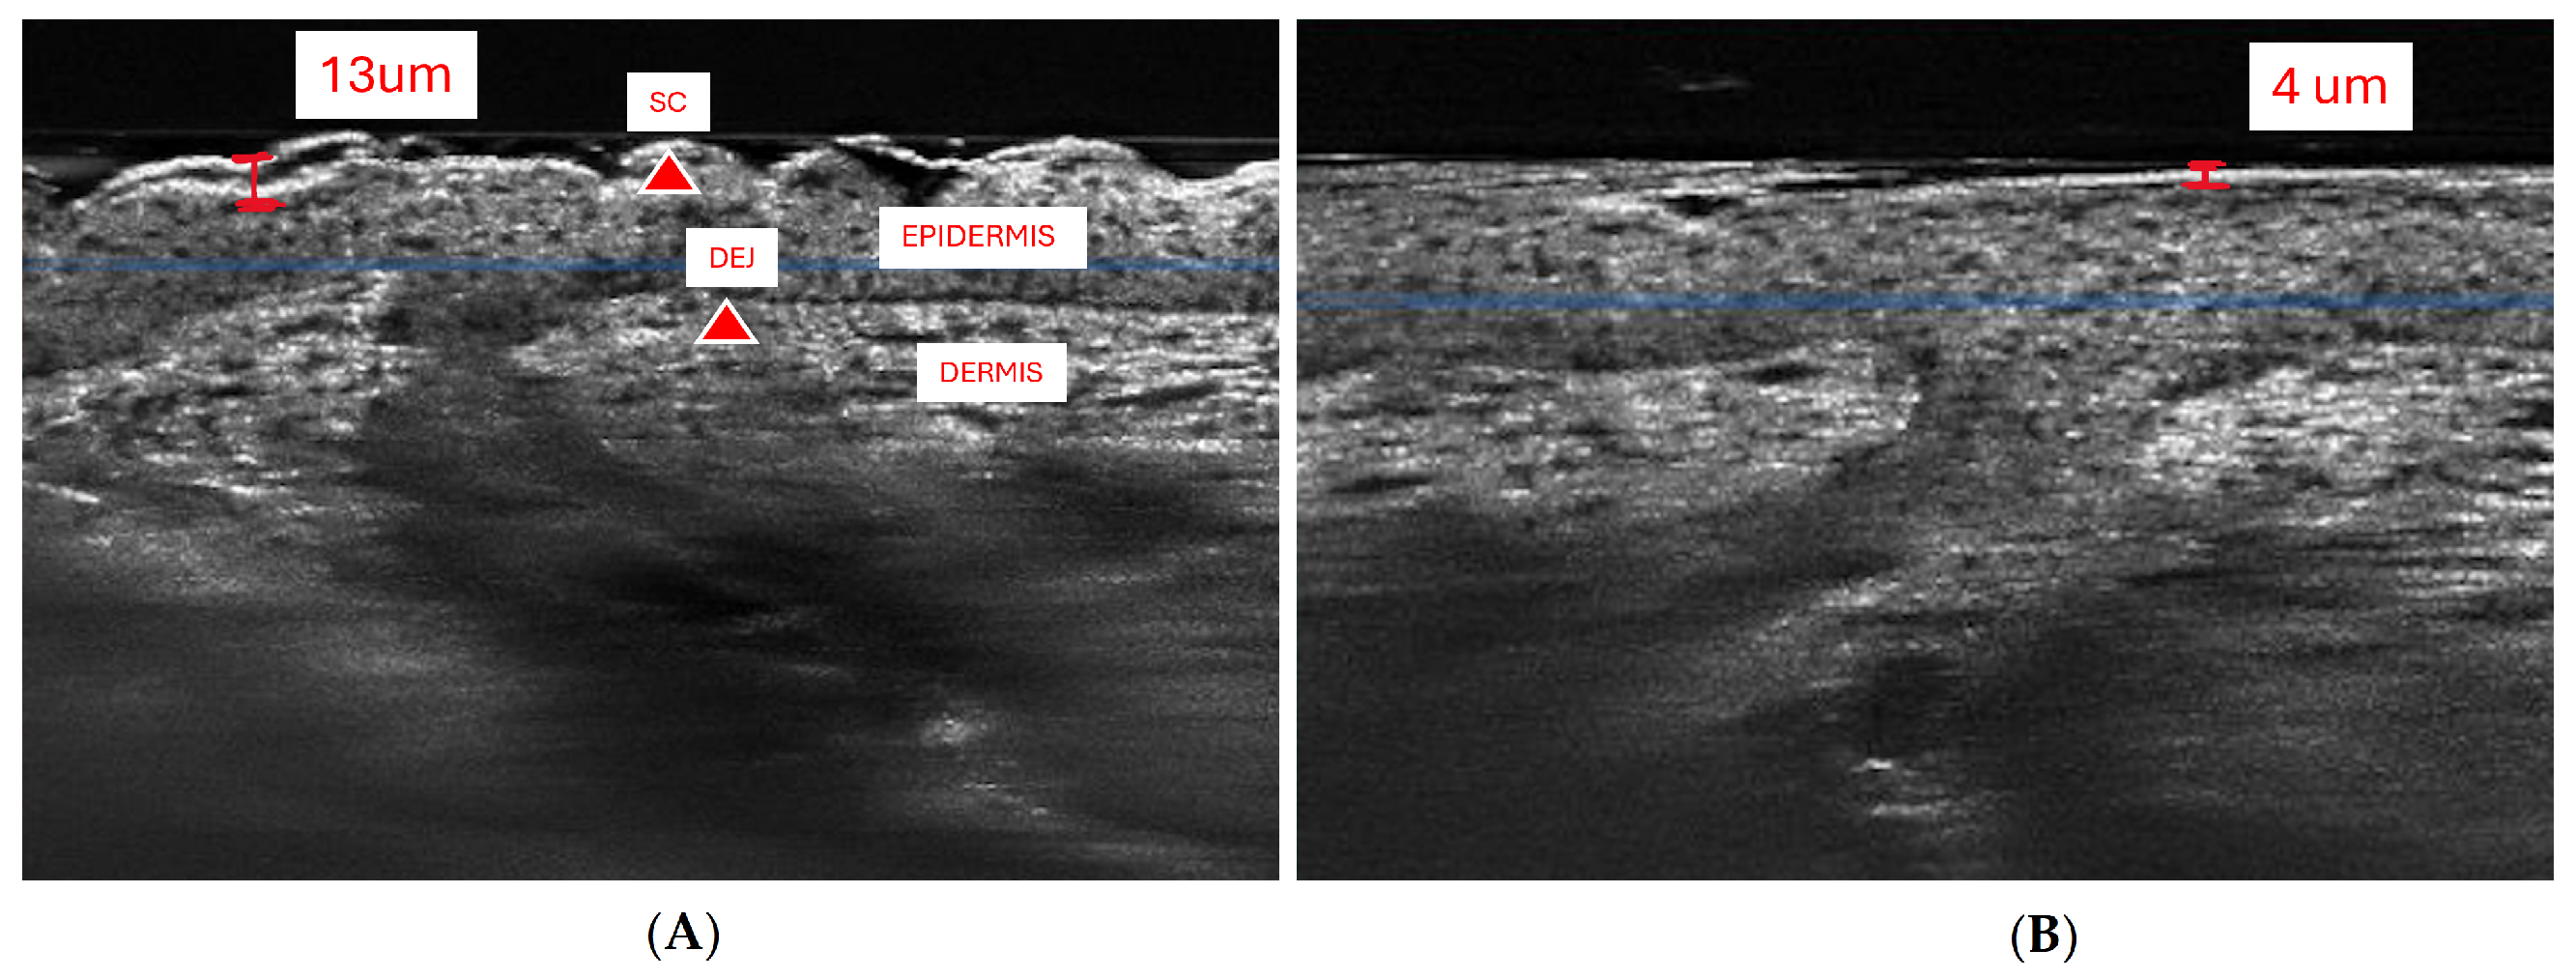

2.4.3. Image Analysis

We analyzed and compared the images of skin before and after treatment with different formulations of adapalene gel. The 2D vertical image was segmented into skin surface, SC, and dermoepidermal junction (DEJ) by a trained confocal microscopy technician. Using these segmented images, three random points were measured for SC thickness and living epidermal thickness (excludes SC) per image and averaged. The corresponding LC–OCT images are presented in Appendix A. Figure A1 presents a vertical (cross-sectional) view of the patient’s baseline skin, clearly distinguishing the epidermis and dermis. Figure A2 shows a representative horizontal LC–OCT image of the patient at baseline, capturing approximately 60 µm in depth. This view prominently highlights features such as the hair shaft and keratinocyte nuclei. The infundibular area of the hair follicle and the isthmus area of the hair follicle were calculated from 9 to 10 random hair follicles per application site for each time point, and the percentage change in the infundibular area to the isthmus area was calculated. Hair follicle infundibular cross-sectional area () and hair follicle isthmus () were measured at the epidermis and dermis level, respectively Figure A3. Keratinocyte count was automated using the open-source software CellProfiler (https://cellprofiler.org/, accessed on 27 September 2024) with the development of a customized pipeline for quantification of keratinocyte nuclei and keratinocyte cytoplasm in Line-Field Optical Coherence Tomography (LC–OCT) images.

3.5. Clinical Studies

To further assess the epidermal response of adapalene in vivo, we used a prospective observational clinical study to evaluate the structural effects of the three different brands of adapalene gel on visually healthy skin. A limitation of excised skin models, such as cadaver skin for penetration studies, is that follicular penetration is reduced due to contraction of elastic fibers [11,31]. This study utilized Line-Field Confocal Optical Coherence Tomography (LC–OCT) to visualize the skin for quantification and visual analysis of structures of interest such as the SC, epidermis, dermis, and follicular and infundibular areas. DeepLive LC–OCT is an imaging technology established by DAMAE Medical (Paris, France), consisting of broadband laser and vertical scans that provide high axial resolution (OCT) with microscope objectives [32]. In addition, it also utilizes line illumination and detection for the high lateral scanning resolution used in reflectance confocal microscopy. The combination of these techniques allows for ultrahigh-resolution 3D scanning [32]. Unlike traditional histopathology, LC–OCT allows for a detailed study of various skin pathologies and their response to treatment over time, without the need for biopsy for histopathologic correlation. The SC thickness was significantly decreased at the 48 h time point (Figure 11) for all formulations (Differin, p = 0.0035; Effaclar, p = 0.0187; Acne Free, p = 0.0104). Additionally, pore size, defined as the percentage change in the infundibular/isthmus cross-sectional area ratio (Differin, Effaclar, Acne Free, p < 0.0001) was decreased at 48 h for all formulations (Figure 12). Our findings align with the changes reflected in clinical studies with cosmetic improvement in skin texture [33]. While many retinoid products claim to improve skin thickness [34], our short term study did not show any statistically significant change in epidermal thickness (Figure A4), keratinocyte area measured by the mean radius (Figure A5), or keratinocyte count within the epidermis (Figure A6). The change in SC thickness and the reduction in pore size was also significantly decreased in the AcneFree group at the 4 to 6 h point, while there was no significant difference at the 4 to 6 h time point with the Differin and Effaclar formulation. However, at 48 h, the change in both parameters was statistically significant in all three formulations.